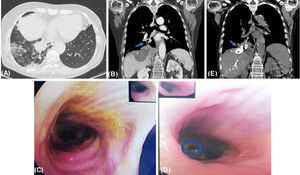

(A) Axial thoracoabdominal-CT image shows ground glass opacities on right lower lobe. (B) Coronal thoracoabdominal-CT image shows new right subphrenic collection contiguous with diaphragm, consistent with an abscess; multiples focal hepatic lesions, one extending to right lung base, with a fistulous track (arrow). (C) Bronchofibroscopy revealed yellowish secretions in all bronchial tree. (D) Bronchofibroscopy revealed mucosa inflammation of medial basal segment of right lower lobe bronchus, from where yellowish secretions flowed, confirming fistulization site (circle). (E) Coronal CT image performed after embolization of the fistulous track shows the presence of high-attenuation embolization material (metallic coils and cyanoacrylate glue) in the right subphrenic space extending into the thorax (arrow).

64-Year-old female presented at emergency department with several days-evolution of cough, yellowish sputum and fever. She had history of colon cancer with lung and hepatic metastases, submitted to multiple surgeries and chemotherapy. Thoracoabdominal-CT scan revealed a new right subphrenic collection contiguous with diaphragm, consistent with an abscess, and multiples focal hepatic lesions, one extending to right lung base, with multiple ground glass opacities (Fig. 1A and B). Therefore, the patient started antibiotic treatment and performed CT-guided percutaneous drainage of subphrenic collection, macroscopically compatible with bile. Bronchofibroscopy showed mucosa inflammation of medial basal segment of right lower lobe bronchus, from where yellowish secretions flowed (Fig. 1C and D), confirming biliobronchial fistula (BBF). Despite considering to close BBF through bronchofibroscopy, due to its peripheral location, embolization of fistulous track through percutaneous transhepatic cholangiography was performed, confirmed in post-procedure CT (Fig. 1E). The patient partially recovered and refused other treatments, being under palliative care.